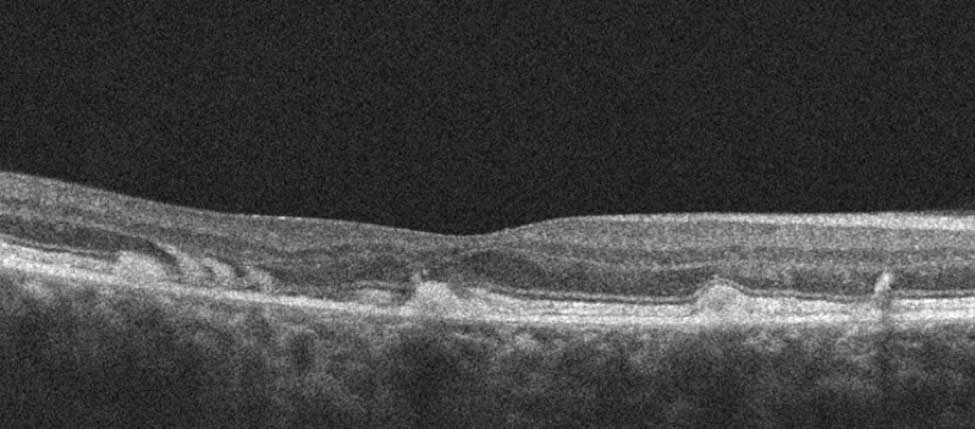

Here there is loss of the regular macular depression. There is a bright line present on the surface of the retina. In addition, there is separation of the retinal layers in the inner retina.

The patient was diagnosed with a schisis secondary to an epiretinal membrane. This complication is seen in over 50% of ERMs (video).

In any patient with intraretinal fluid consider the possibility of an epiretinal membrane causing a schisis.